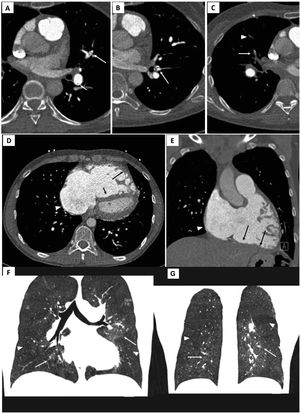

The target lesions for each session are selected by matching the perfusion defects on V/Q scan, and lesion morphology in DSA and CTPA (Figure 7), which are later confirmed through segmental pulmonary angiography. In the first sessions, the lobe with the worst perfusion is often the target. If there are multiple perfusion defects, the treatment of lower lobe lesions where perfusion is greater and, consequently, with higher potential to reduce mean PAP, are selected for first BPA procedures. The treatment of less complex lesions such as ring-like stenosis, webs and subtotal lesions are favored. Total occlusions and tortuous vessel injuries are less frequently addressed during the first sessions, due to high risk of vascular injury. As mentioned by Matsubara et al.,24 total occlusions although more difficult to intervene and more likely to cause vascular injury, are also related to superior hemodynamic improvement when compared to less stenotic lesions. Increasing the number of treated segments, as well as addressing difficult lesions are both needed to improve the efficacy of BPA.24 Therefore, the treatment of total occlusions can be carried out in later sessions, when pulmonary hemodynamics have improved.

Electrocardiogram-gated pulmonary computed tomography (CT) angiography of patients with chronic thromboembolic pulmonary hypertension. Upper panel: A) and B) axial images showing hypodense linear structures forming webs and bands, inside the lumen of arteries, consistent with residual thrombus; C) demonstrates luminal opacities and marked caliber reduction of segmental vessels, suggesting subtotal lesion, as well as marked stenosis of more distal, subsegmental vessels (arrowhead).

Middle panel: D) Pulmonary CT angiography depicting right atrial dilation (arrowheads) and leftward deviation of the interventricular septum (short arrow) yielding a “D-shaped” left ventricle. D and E) right ventricular dilation and hypertrophy (long arrows show free wall thickening) with marked myocardial trabeculation.

Lower panel: F and G) Mosaic pattern of lung attenuation. The hypoperfused (oligemic) lung appears lower in attenuation (arrowheads) than adjacent normal perfused lung (arrows).